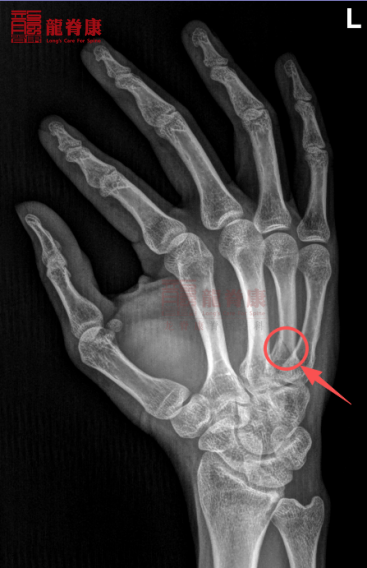

2、X光片检查

左手正斜位DR阅片示:考虑左手第四跖骨近端骨折。

图片